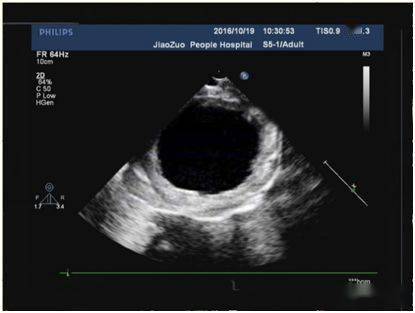

心内膜胶原弹力纤维增生症 (endocardial fibroelastosis,efe) 是指心

心内膜弹力纤维增生症